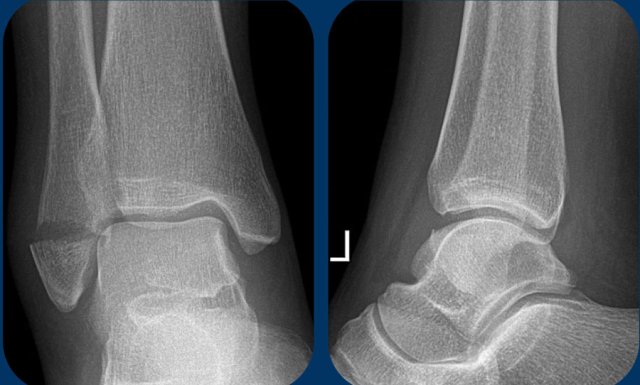

Stage 1: stable ankle fracture Stage 1: stable ankle fracture

Stage 1

Here a typical avulsion or pull-off fracture of the lateral malleolus.

The avulsion fragment is quite large. More commonly there is a small avulsion fragment.

This is a stage 1 stable Weber A fracture.